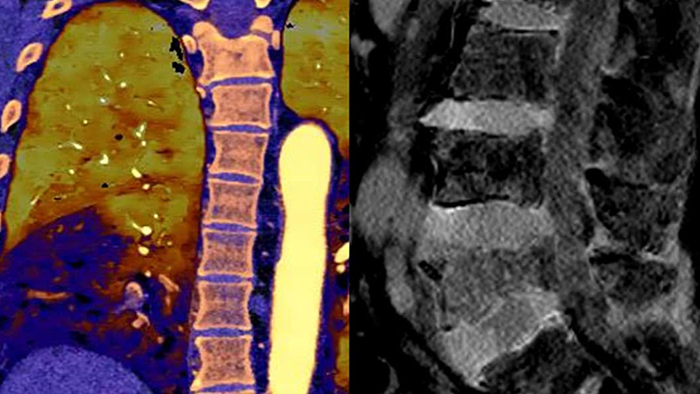

通常どおりにスキャン いつでもどの患者に対しても、1回の高速な低線量スキャンで標準データおよびスペクトラルデータを取得できます。

常に使用可能 スペクトラルデータは常に100%使用可能であり、検査結果はいつでも、オンデマンドだけでなく、レトロスペクティブに取得することもできます。

フォローアップ検査の削減 組織の特性評価と視覚化が改善されることにより、患者の検査が最適でなかった場合や、偶発病変が見つかった場合に、フォローアップスキャンを行う必要性が低減される可能性があります。